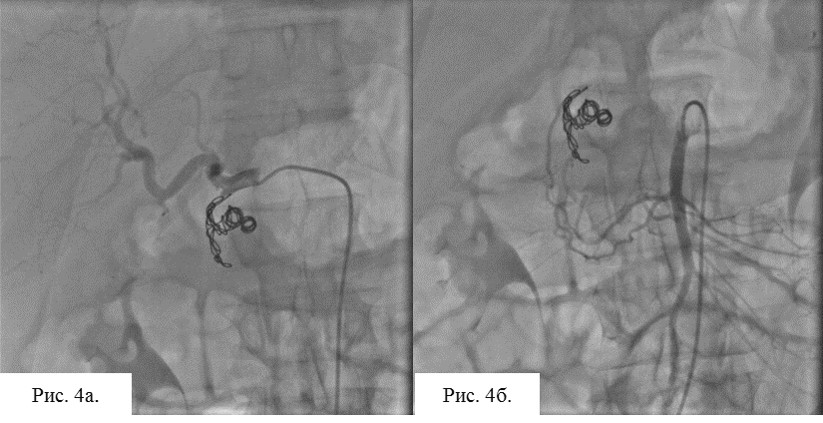

Сразу после проведения диагностической ангиографии, катетером Cobra 3 (C3) фирмы Terumo, выполнена эмболизация желудочно-двенадцатиперстной артерии, ложной артериовенозной аневризмы, в том числе и в области сброса в портальную систему. При проведении РЭО использовались спирали Azur 35 – 10 см.

При контрольной съёмке из общей печёночной артерии, а так же из системы панкреатодуоденальных артерий бассейна ВБА, отмечается стойкая редукция кровотока.

Рис. 4 а. Визуализация области окклюзии из общей печёночной артерии бассейна чревного ствола. Отмечается стойкая редукция кровотока.

Рис. 4б. Визуализация области окклюзии из верхней брыжеечной артерии. Отмечается стойкая редукция кровотока.